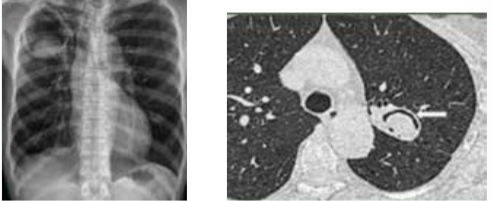

What is the radiological diagnosis in pneumothorax?